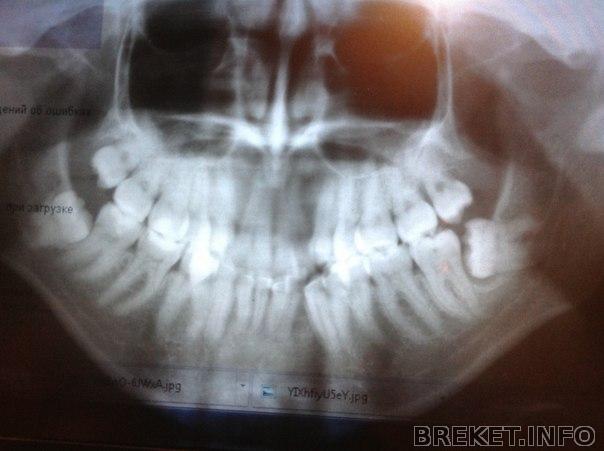

. Прошло уже две недели после последней консультации, а все не могу заставить себя пойти удалить эту ужасную восьмерку!! Не знаю, что с собой сделать, не могу и все! Мне страшно! Ненавижу себя за это!!Была на консультации у хирурга в хорошей клинике, так она отказалась браться за такой сложный зуб! Сказала, что он на нерве сидит.... В другой клинике хирург согласен ее удалять, но сказал, что удаление сложное (часа на два) и желательно сделать это под общим наркозом! А наркоза я боюсь еще больше (т.к. он с ИВЛ)! Не знаю, что делать... Есть вариант удалить ее под седацией (внутривенное успокоительное снимает эмоции и чувство страха, без побочных эффектов) в той же клинике. Осталось только набраться смелости)) никогда ничего не удаляла, а тут сразу такой зубище

У меня наверно так не получится, т. к. удалять будут четверки или пятерки на НЧ. Ортодонт сказала, что ни одна из восьмерок не помешает исправлению прикуса, но та горизонтальная может повредить семерку и еще она под капюшоном и туда все время еда забивается.

Katie24, тогда наверное действительно лучше ее удалить!! мои то даже не наклюнулись еще-сидят себе в косочке и только на снимке мне "привет" передают)